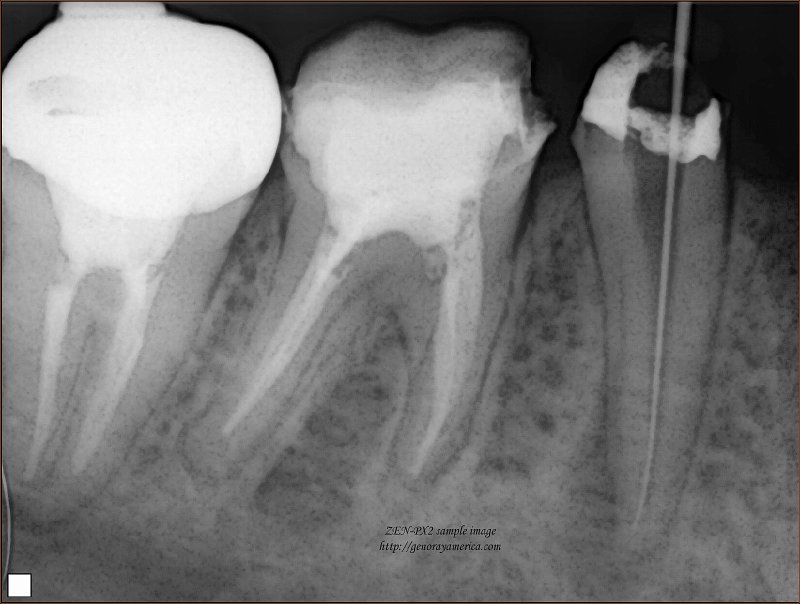

Несколько слов о кариесе и его рентгенодиагностике. Кариес – заболевание зуба, проявляющееся снижением минерализации и прогрессирующим разрушением твердых тканей зуба с образованием дефекта ткани (кариозной полости). Заболеваемость кариесом достигает 100%. Осложнения кариеса – пульпит (воспаление в пульпе зуба) и периодонтит (воспаление тканей, окружающих зуб). Кариес может поражать один, несколько или все зубы. Обычно кариозные полости хорошо видны при осмотре. Рентген делается для того, чтобы выявить размер и глубину кариозной полости, оценить состояние окружающих зуб тканей, диагностировать кариозные поражения под пломбами и коронками, на корнях зуба, проконтролировать правильность заполнения кариозной полости пломбировочным материалом, оценить состояние ранее выполненных пломб.

При лечении и пломбировке корней зубов рентгенограммы выполняют для оценки проходимости корневого канала и качества пломбировки. Поскольку при неполной пломбировке канала в дальнейшем могут возникнуть осложнения и воспаление в месте дефекта пломбы. В процессе лечения рентгенограмма может быть выполнена с введенными в корень зуба корневыми иглами.